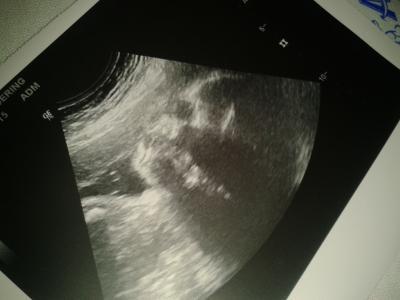

Junior hatte so gar keine Lust auf ein CTG. Er verschwand ständig...kleiner Schlingel Danach gabs noch einen Ultraschall und er hat sich natürlich wieder ganz prächtig präsentiert, so dass mir die Ärztin nicht nochmal bestätigen musste, dass es ein Junge wird Tja während des US (er lag am Anfang in SL) drehte man sich um, weil der Schallkopf wohl am Köpfchen störte und lag dann in BEL...er war so zappelig und trotzdem konnte man so viel sehen und ich bin immer wieder davon fasziniert. Auch sah man eine Stupsnase und irgendwie (auch wenn es nur der graue US war) sah er aus wie mein Mann, ich bin gespannt ob es dann auch wirklich so ist :) Junior findet wohl auch seine Füße ganz toll, denn die hat er uns heute wieder total süß im US gezeigt Er ist ca. 40 cm groß, wiegt ca. 1700 Gramm und der KU soll wohl bei 30 cm liegen. Dickkopf eben (der Kopf ist laut dem US auch fast 2 Wochen weiter). Ich bin gespannt was am Ende raus kommt :)

Bild zu Zurück vom FA + Bild - Forum für Mai - Mamis